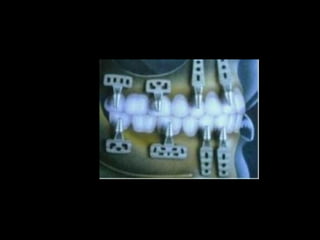

Colocación de la prótesis dentaria.

Estructuras metálicas subperiósticas:

Tornillos para fijación en hueso:

Prótesis:

• Los implantes subperiósticos son parte de la historia de la

Odontología, sin embargo en su momento fueron una buena

solución para casos protésicos difíciles.

Colocación de laprótesis dentaria.

Estructuras metálicas subperiósticas: Tornillospara fijación en hueso: Prótesis:

Estructura implantada pordebajo del periostio:

• Los implantessubperiósticos son parte de la historia de la Odontología, sin embargo en su momento fueron una buena solución para casos protésicos difíciles.